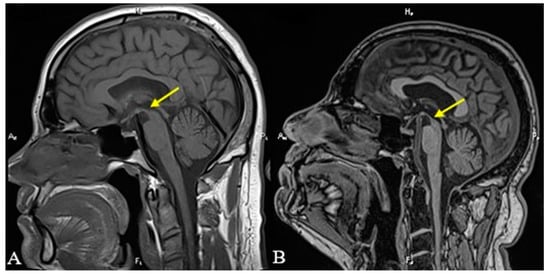

| Positive “hummingbird” sign. |

| Midbrain-to-pons ratio = 0.37. | ||||